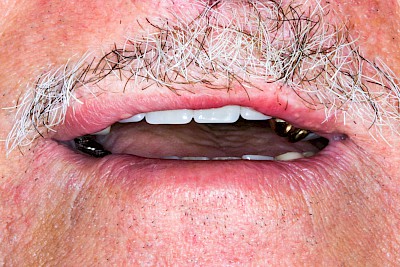

Gehen die Zähne verloren, baut häufig auch der Kieferknochen ab (Knochenschwund). Die Geschwindigkeit und das Ausmaß des Knochenschwundes ist von vielen Faktoren abhängig. Neben der genetischen Veranlagung spielen auch Überbelastungen in Folge, z. B. bei ständigem Knirschen oder Pressen, eine Rolle. Auch wenn Zahnprothesen Tag und Nacht getragen werden, kann die ständige Belastung der Schleimhäute und des Knochens den Knochenschwund beschleunigen.

Aber Achtung: Manche Menschen fühlen sich ohne Zahnprothesen unwohl. Zudem kann es passieren, dass Zahnprothesen (wenn noch eigene Zähne vorhanden sind) nicht mehr passen. Dies gilt vor allem dann, wenn diese Zahnprothesen nicht nur über Nacht, sondern für einen längeren Zeitraum nicht mehr getragen werden.

In jedem Fall sagen die Betroffenen, dass es sich ein paar Minuten komisch anfühlt, wenn sie die Zahnprothesen über Nacht aus dem Mund nehmen und dann morgens wieder einsetzen. Das ist normal und liegt daran, dass die Schleimhäute sich wieder regenerieren. Das ist gut für die Schleimhäute und Knochen im Bereich der Kiefer. Wir gehen ja auch nicht mit Schuhen ins Bett!

Auch wenn Zahnprothesen drücken, sollten vor allem Teilprothesen jeden Tag wenigstens für ein paar Minuten getragen werden, damit sich die eigenen Zähne nicht unbeabsichtigt verstellen und die Prothese weiter passt.